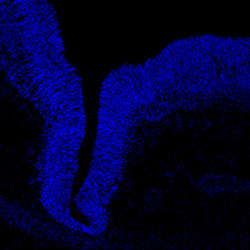

DAPI

11PCW human midbrain